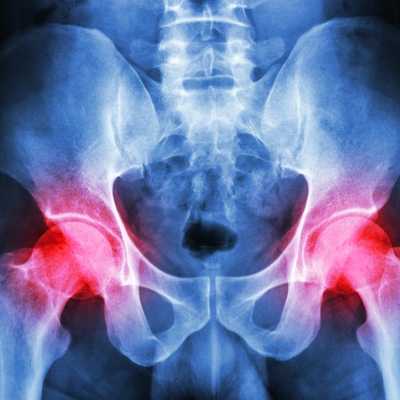

Click on an image below to view more info.